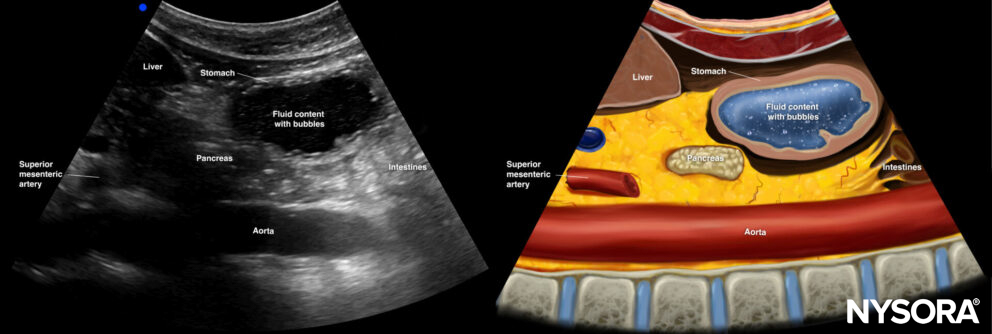

Fluid content

The presence of intraluminal fluid will result in a rounded and distended appearance of the antrum and thin stomach walls. Sonographically, a differentiation can be made between clear fluids and non-clear fluids (e.g., suspensions or milk). Clear fluids are anechoic, whereas non-clear fluids are hyperechoic.

Ultrasound and Reverse Ultrasound Anatomy of a stomach with fluid content.

Tip

The ingestion of carbonated fluids may result in a transient image with bubbles, also known as the ‘starry night’ appearance.